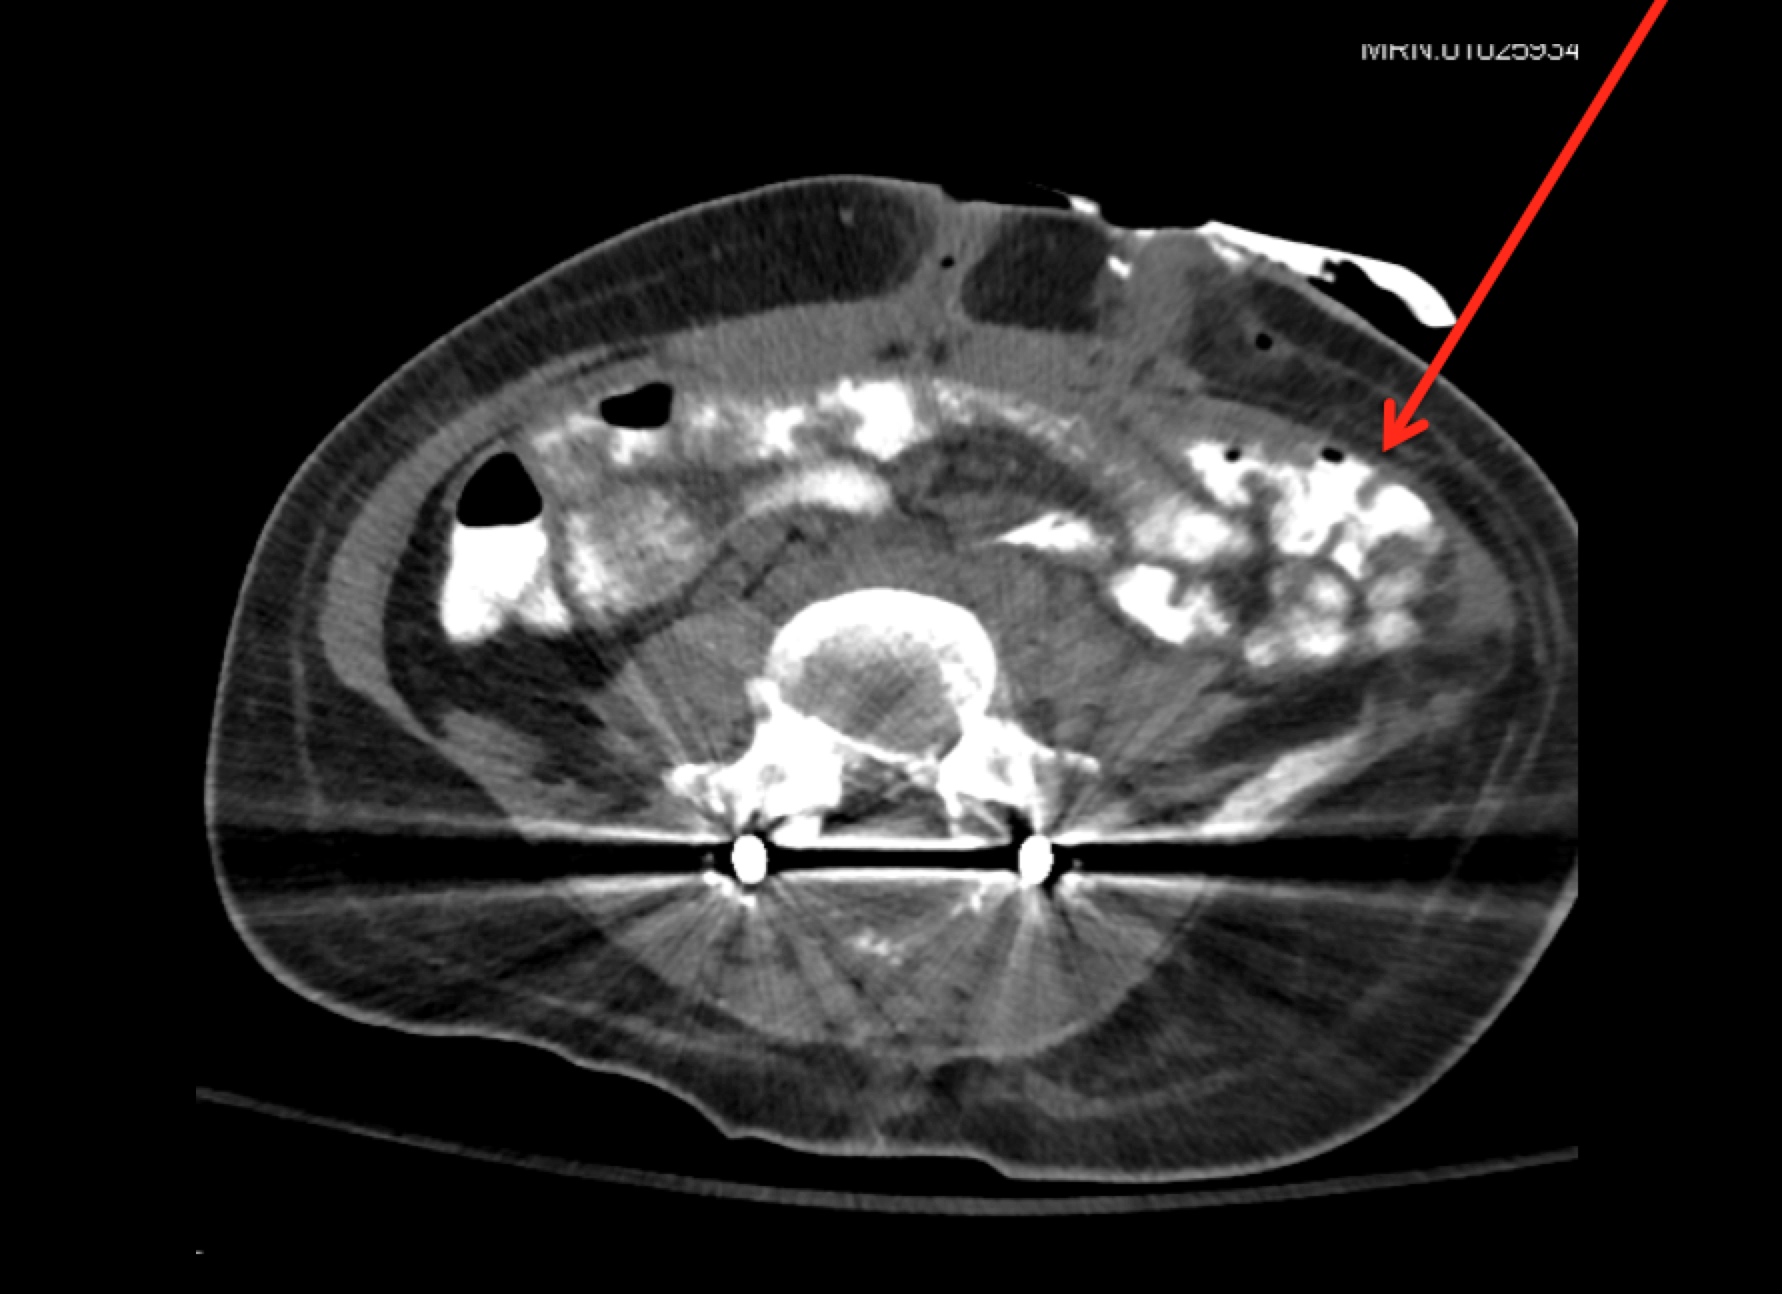

Approach to the Patient with Glomerular Disease

- Serologic diagnosis of glomerular diseases (e.g., anti-GBM antibody, ANCA, anti-PLA2R antibody)

- Use of dysmorphic hematuria (by microscopy of urine sediment to detect glomerular disease

- Investigation of serum complement abnormalities as clues to underlying disease

- Improved analysis of renal biopsy material, leading to a more accurate diagnosis and/or prognosis